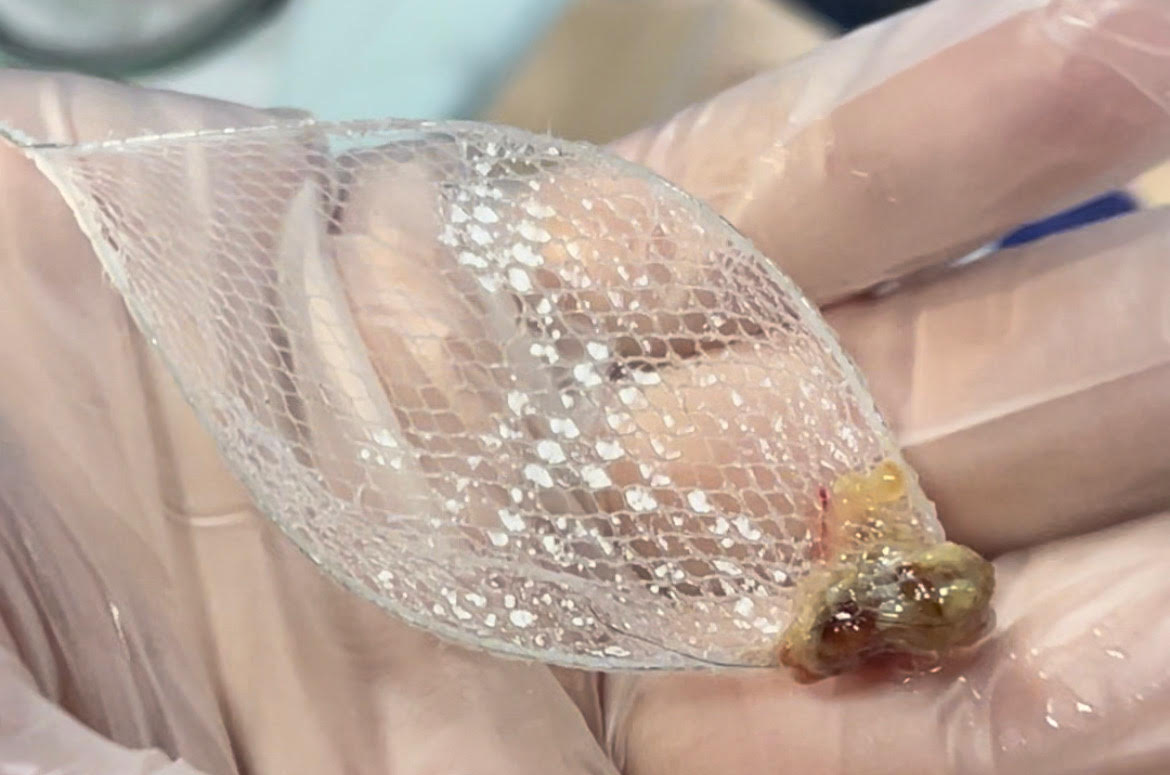

ستێنتکردن لە نەخۆشێکدا کە تەسکبوونەوەی لوولەی هەناسەی هەیە

وۆرک شۆپی پراکتیکی ستێنتکردنی سییەکان